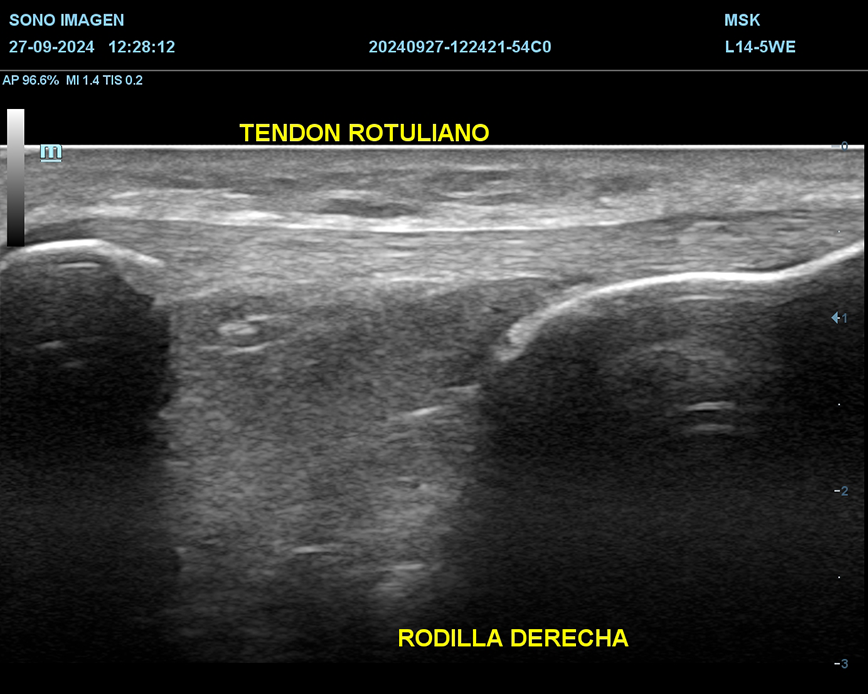

Ecografía de rodilla

- evaluación del dolor de rodilla

- lesiones de tejidos blandos: tendinosis, desgarros ligamentosos, rupturas meniscales.

- derrame articular

- inflamación o infección

- evaluación de lesiones deportivas

- quiste de Baker

- seguimiento postoperatorio

- traumatismos